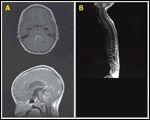

FIGURE 5

High-Grade Glioma

High-grade glioma including anaplastic astrocytoma (WHO grade III) and glioblastoma multiforme constitute about 14% of CNS tumors in children. These tumors can occur anywhere in the brain. In a recent Children's Cancer Group (CCG) study report of 131 evaluable children with high-grade glioma, over 90% of tumors occurred in a supratentorial location (63% in the superficial cerebral hemisphere and 38% in the deep or midline cerebrum) and only 8% occurred in the posterior fossa, including the brain stem and cerebellum (Figure 5).[53]